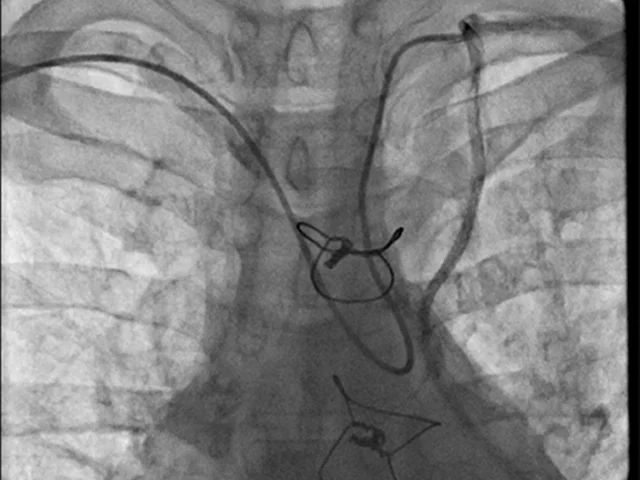

POST CABGs

From Radial

Culotte Stenting

LM - 3VD Lady